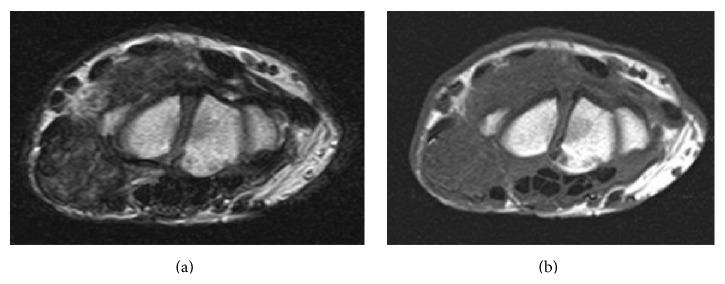

Introduction. Tumoral calcium pyrophosphate dihydrate (CPPD) crystal deposition disease (CPPDCD), also known as tophaceous calcium pyrophosphate deposition disease (CPDD), is a tumorlike lesion, and it should be distinguished from usual CPDD that causes severe joint inflammation and arthralgia. A case of tumoral CPPDCD of the wrist joint that required differentiation from synovial osteochondromatosis is described. Case Presentation. The patient was a 78-year-old woman with a 5-year history of nodular lesions at the right wrist that had gradually increased in size. An excisional biopsy and a histological examination of the excised nodular lesions by hematoxylin and eosin (H&E) staining were performed, demonstrating numerous polarizable, rhabdoid, and rectangular crystals, surrounded by fibroblasts, macrophages, and foreign body-type giant cells, consistent with tumoral CPPDCD. Conclusion. Tumoral CPPDCD, especially at the wrist joint, is rare, and, to the best of our knowledge, only 2 articles have been published. This case seems to need further follow-up for recurrence, because tumoral CPPDCD may recur after complete or incomplete surgical excision.